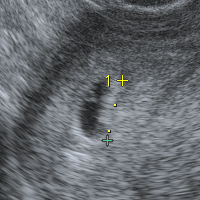

妊娠4週目のエコー写真とママの気持ち 胎児 ママの状態は 注意点は ママズアップ

妊娠4週目 4w0d 6d のエコー写真とエピソード 妊娠2ヶ月 Cozre コズレ 子育てマガジン

妊娠4週目のエコー写真 胎芽や胎嚢 初期症状や流産のこと 妊娠初期 All About

マタニティライフ 妊娠から出産までの記録 妊娠4週目エコー画像

妊娠4週0日 4w0d の超音波 エコー 写真

妊娠4週4日 エコー写真 私と赤ちゃんと時々し ちゃん

妊娠4週 3 6日 のエコー写真 体験談

妊娠4週3日 4w3d の超音波 エコー 写真

妊娠4週4日 4w4d の超音波 エコー 写真

妊娠4週 赤ちゃんのエコー写真 超音波写真まとめ たまひよ